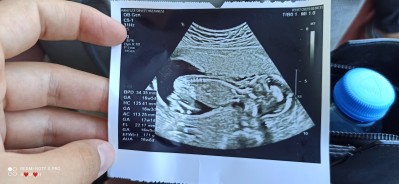

16 haftalık fotoğraf secde pozisyonunda olduğu için doktor net bir şey söyleyemiyorum dedi

Yuz  ustu   yatmis  ve  bacaklari  toplu  sekilde  bacak  arasi  gorunmez   bu   sekilse  o  yuzden  tahmin  yapmamistir  bende  goremwdim

Kesesi erkek kesesine benziyi. Omurga kemiği de çok belirgin büyük ihtimal erkek bence